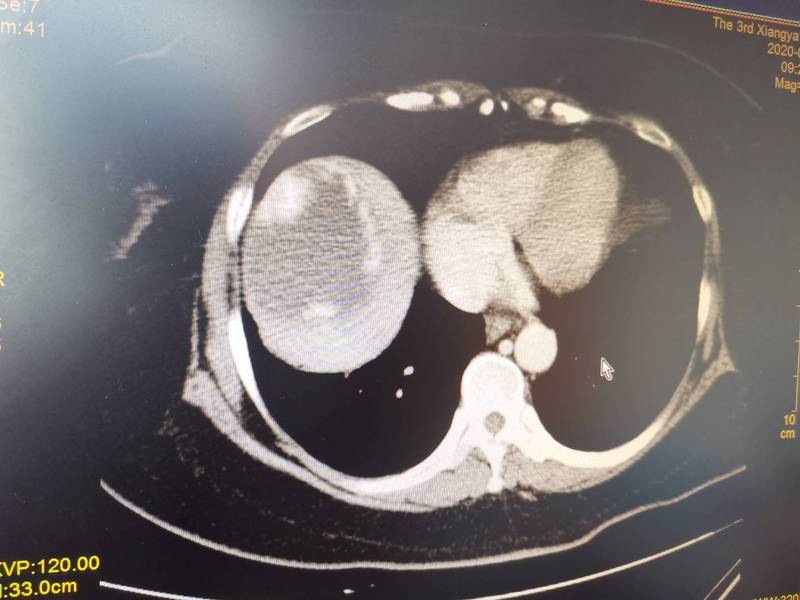

此病例肝臟血管瘤合并膽囊多發(fā)結(jié)石并慢性膽囊炎,外院轉(zhuǎn)入,肝血管瘤五年內(nèi)從兩厘米長到八厘米,主要位于第八段,在熒光腹腔鏡引導(dǎo)下行右肝血管瘤切除加膽囊切除術(shù)。熒光腹腔鏡在血管瘤的引導(dǎo)上功不可沒,確實(shí)有他的優(yōu)勢 肝臟血管瘤臨床上非常常見,很多人都有,建議第一次彩超發(fā)現(xiàn),不典型的可以做ct或者mri確診, 肝血管瘤的手術(shù)指證越來越嚴(yán)格,我印象從六厘米到八厘米,目前指南基本定在十厘米,但是不是絕對的,對于有癥狀,導(dǎo)致其他問題如壓迫等,或者像本例進(jìn)行性增大的還是需要手術(shù),作為一個良性疾病,腹腔鏡切除確實(shí)有很大的優(yōu)勢,創(chuàng)傷小,恢復(fù)快,術(shù)野清晰,術(shù)中失血少,但是對手術(shù)團(tuán)隊(duì)的要求相對較高,麻醉科和手術(shù)室護(hù)士支持也非常重要!